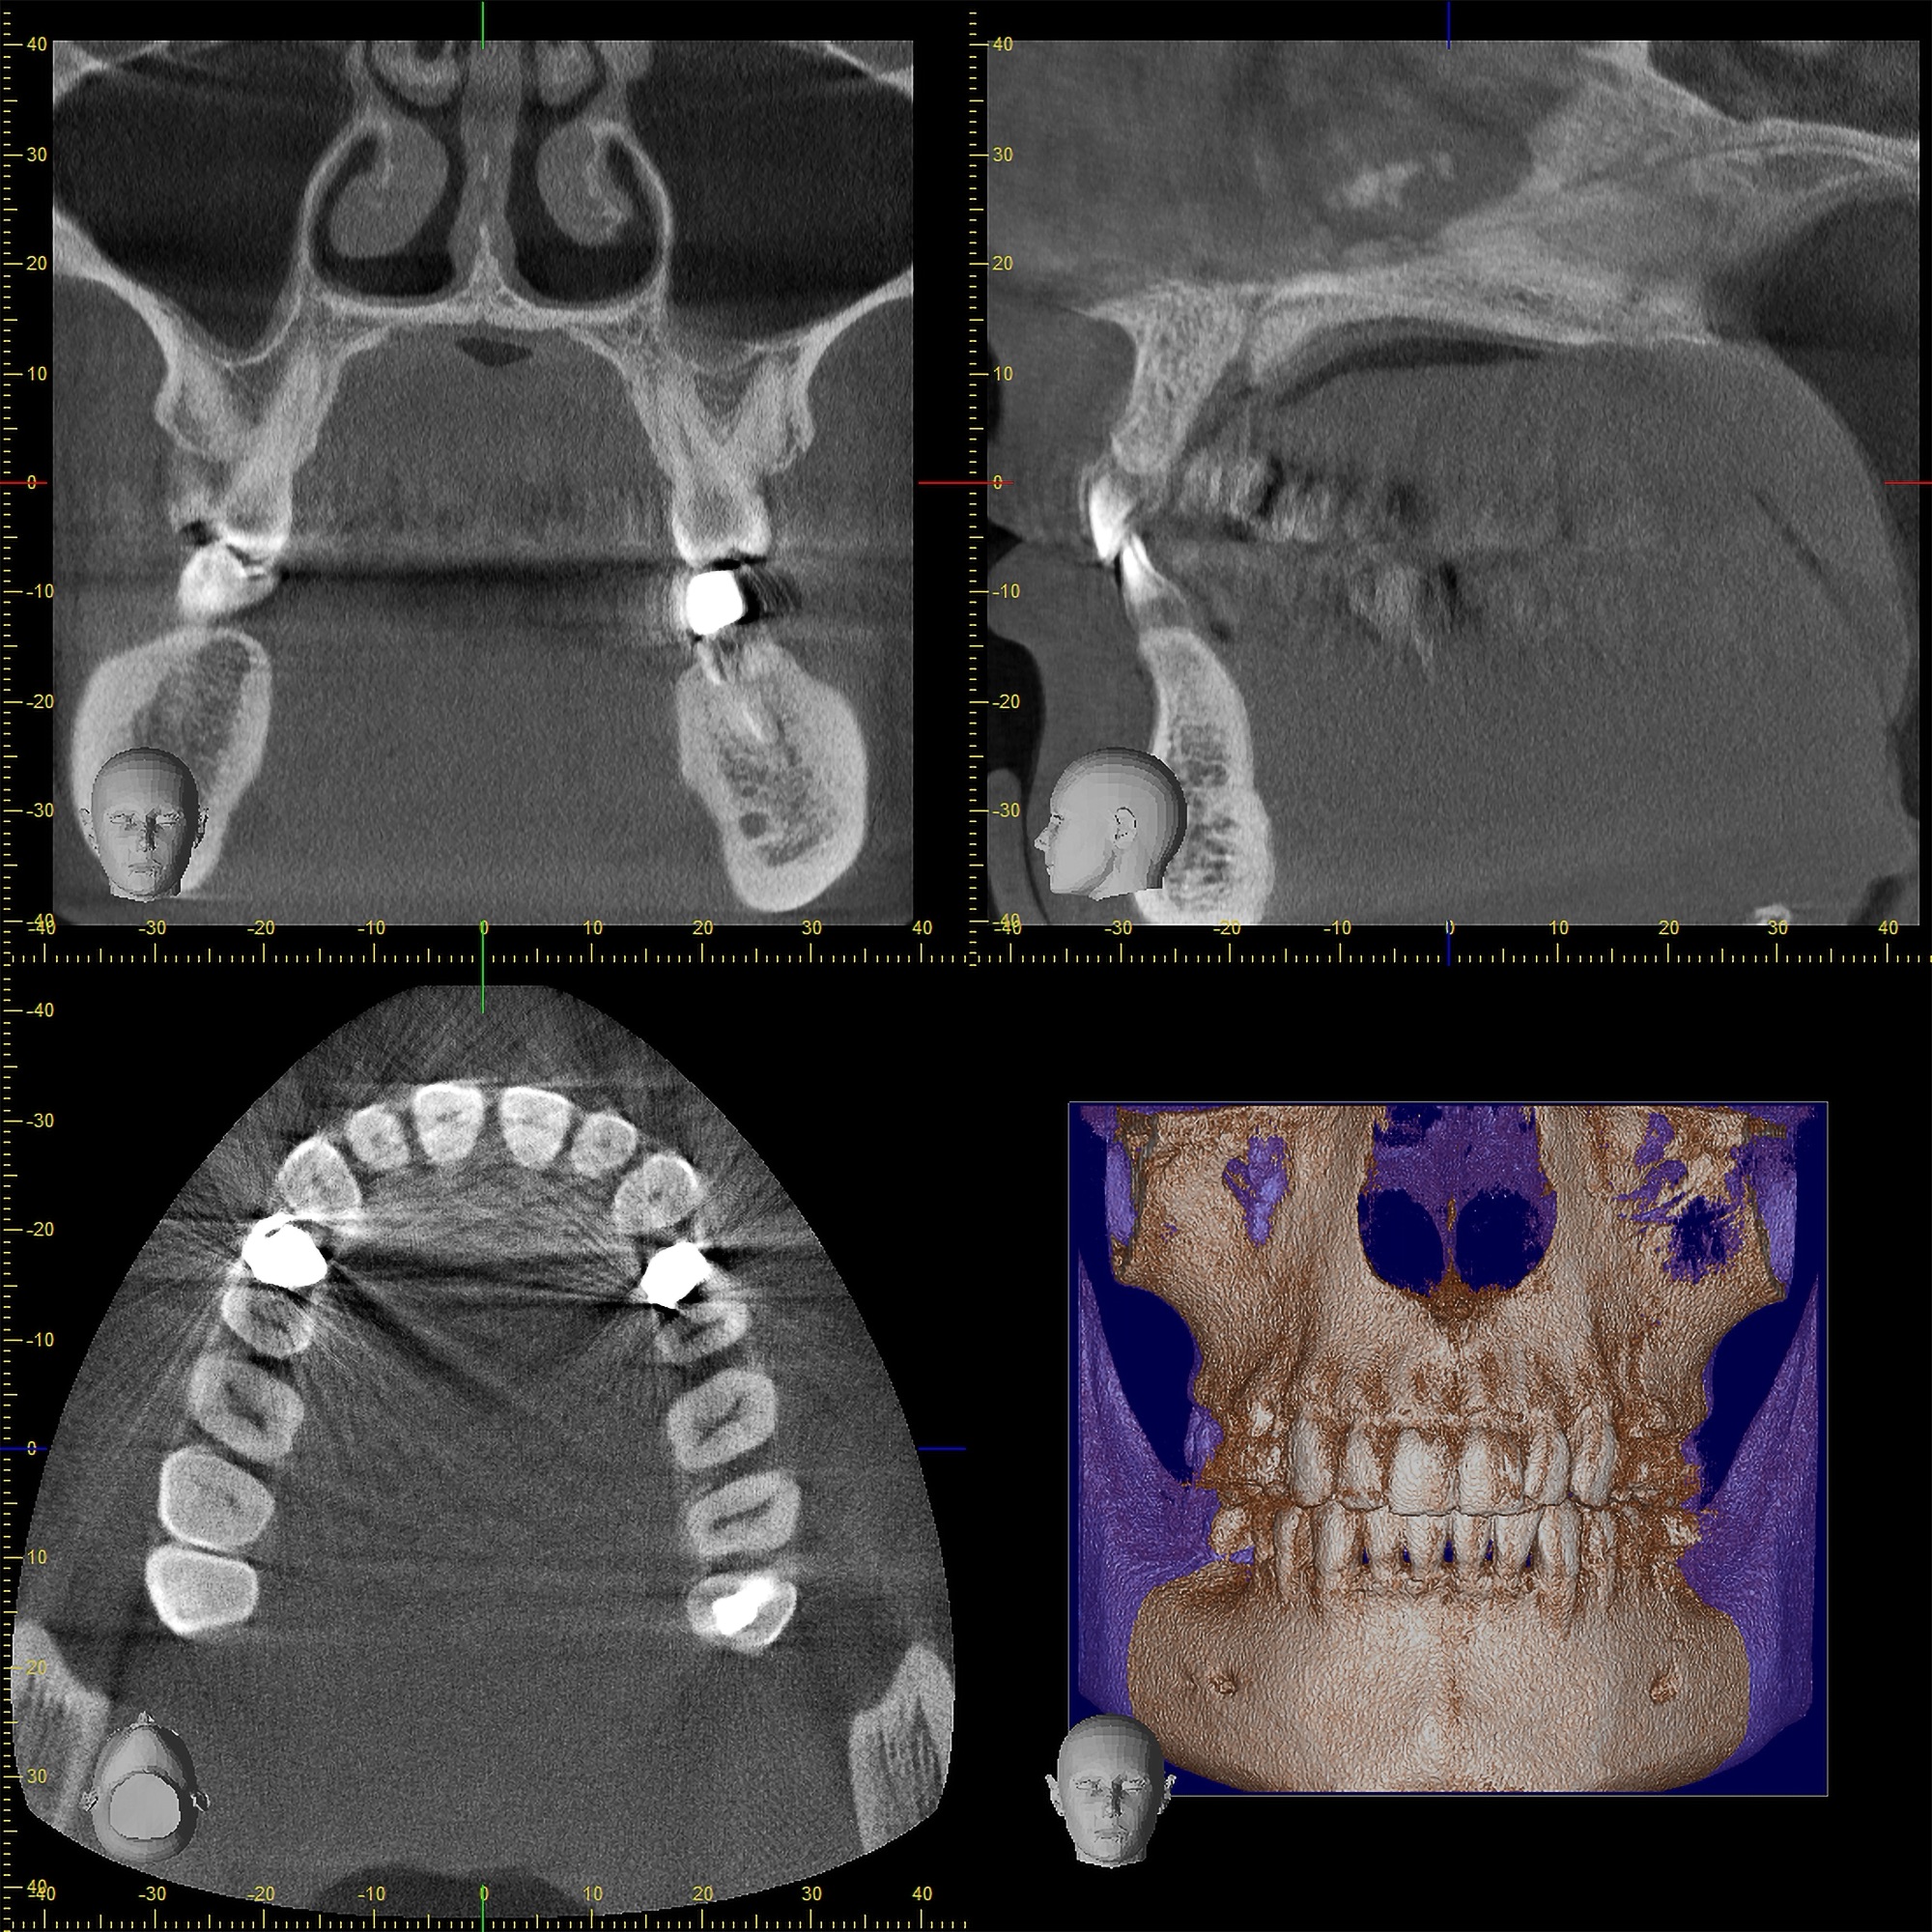

歯科用CTによる精密なシミュレーション

横向きに生えた歯(水平埋伏智歯)の抜歯で最も重要なのは、事前の診断です。最新の歯科用CTを用い、指導医が神経や血管の位置を3次元的に解析。ミリ単位の精度で安全な手術ルートを決定します。